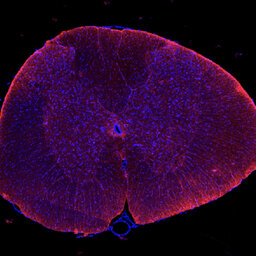

Clinical Trials and Research on Spinal Cord Injury

Join us for an engaging podcast where we delve into the latest advancements in spinal cord injury (SCI) research, with a special focus on children. In this episode, we are honoured to feature two esteemed experts: Professor Mary Galea, Professorial Fellow in the Department of Medicine at the Univer…